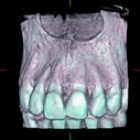

対するCT写真は3次元的な画像を撮れるので、対象物を輪切りにして見たり、様々な方向から立体的に評価する事ができます.これにより、例えば顎の骨の中をどのように神経や血管が走行しているか、骨の厚み、密度、歯の中の神経の形、歯の根っこの先の曲がり具合など、詳細に評価できるので、手術を安全かつ安心して受けて頂く事が可能になります.